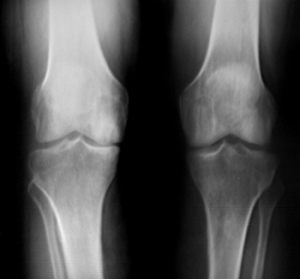

Radiological Testing

X-rays can help in the diagnosis and may be the only special test required in the majority of cases. X-rays can also help doctors rule out other problems, since knee pain from OA may be confused with other common causes of knee pain, such as a torn meniscus or kneecap problems. In some cases of early OA, X-rays may not show the expected changes.